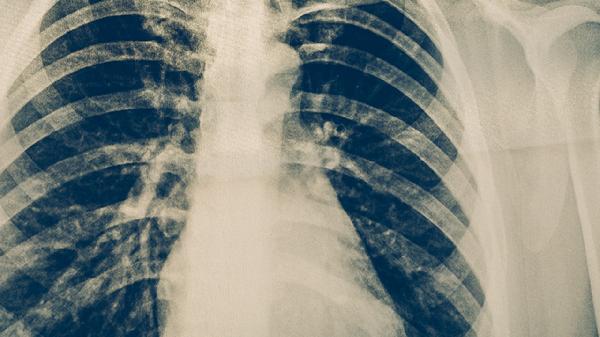

肺结核是由结核分枝杆菌引起的慢性传染病,痰菌转阴是评估治疗效果的重要指标。规范抗结核治疗1-2个月后,多数患者痰涂片检查可转为阴性。若患者严格遵医嘱联合使用异烟肼片、利福平胶囊、吡嗪酰胺片等一线抗结核药物,并保持规律用药,2-3个月内可实现痰菌转阴。治疗期间需定期复查痰涂片和痰培养,动态监测菌量变化。部分患者因药物敏感性差异、合并糖尿病等基础疾病或存在耐药菌株,转阴时间可能延长至3-6个月。早期发现病灶局限、无空洞形成的患者,转阴速度相对较快。

少数患者因治疗不规范、药物不良反应中断用药或感染耐药结核菌,可能导致转阴时间超过6个月。这类情况需通过药敏试验调整方案,必要时采用二线药物如左氧氟沙星片、阿米卡星注射液等强化治疗。合并HIV感染、营养不良或既往结核病史者,免疫状态较差可能延缓转阴进程。对于痰菌持续阳性超过4个月的患者,需警惕治疗失败风险,应及时进行胸部CT评估和耐药基因筛查。